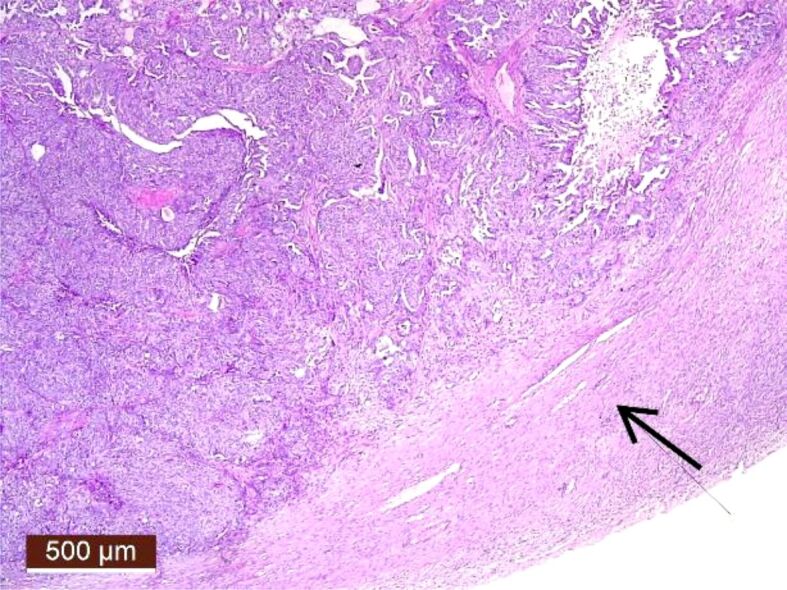

High-grade serous ovarian cancer (HGSOC) with fallopian tube involvement.

Case presentation: We report the case of a 45-year-old woman who had unspecific symptoms of abdominal pain and loss of appetite and weight. A pelvic magnetic resonance imaging was performed, and an ovarian mass was detected. Our case shows that the fallopian tube can be the primary point of origin for a pelvic disease, therefore prevention is possible with early computed tomography scan and annual ultrasound. The patient presented with a T1c staging post-surgery and her chances of survival could have decreased if she had postponed medical examination longer. We found a significant increase in the absolute number of tubal secretory cells in patients with ovarian neoplasia, which supports the assumption that serous tubal intraepithelial carcinoma lesions are found especially in the serous ovarian type.

Conclusions: Our article is a strong suggestion that serous ovarian cancer originates from the fallopian tube and can potentially serve as a sensitive biomarker for early serous carcinogenesis within the fallopian tube.